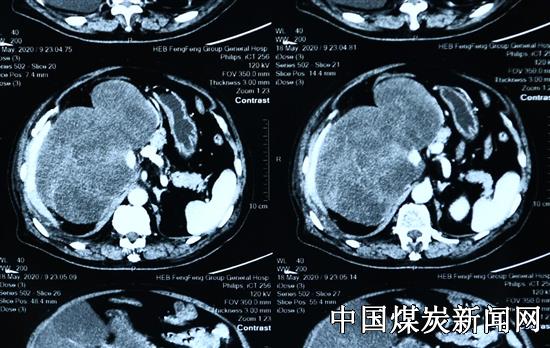

【本网讯】近日,华北医疗集团峰峰总医院外二科经过8个多小时的手术为一位近80男性患者分离和切除腹膜后肝肾间隙的重达10公斤的20*15cm巨大肿瘤,并成功为患者保住右肾。

这名78岁的患者同时患有高血压2级(极高危),还有肺气肿、气管炎、脑梗死后遗症、主动脉硬化,三尖瓣关闭不全及贫血等疾患。患者肿瘤严重挤压下下腔静脉移位,部分肿瘤位于其后方、右肾血管蒂包绕;肿瘤还挤压肝脏、右半结肠等脏器。

术前峰峰总医院外二科认真组织了CT室、麻醉科、彩超室、泌尿外科、肾内科、呼吸科等多学科进行疑难病例的讨论以及科室的术前讨论,详细分析和制定手术方案。在手术中,患者身体里的巨大肿物占据了半个腹腔形状不规则、不能活动,表面血管多且粗大挤压腹腔脏器移位,难以暴露,使手术难度很大。外二科主任张海林认真指导,副主任张浩、姜卫星在护士陈红珍麻醉医师韩伟的长时间配合下,手术步步小心,逐渐细心分离结扎血管防止患者大出血、分离肠系膜、分离与肝脏的粘连、分离被肿瘤包裹的右肾表面及相应动静脉血管、分离下腔静脉,分离肿瘤与各脏器的粘连,把被挤压移位的右半结肠归位......,由于患者贫血术中通过输血及时稳定循环保证患者生命体征,最终医护成功为患者切除这一巨大肿瘤。